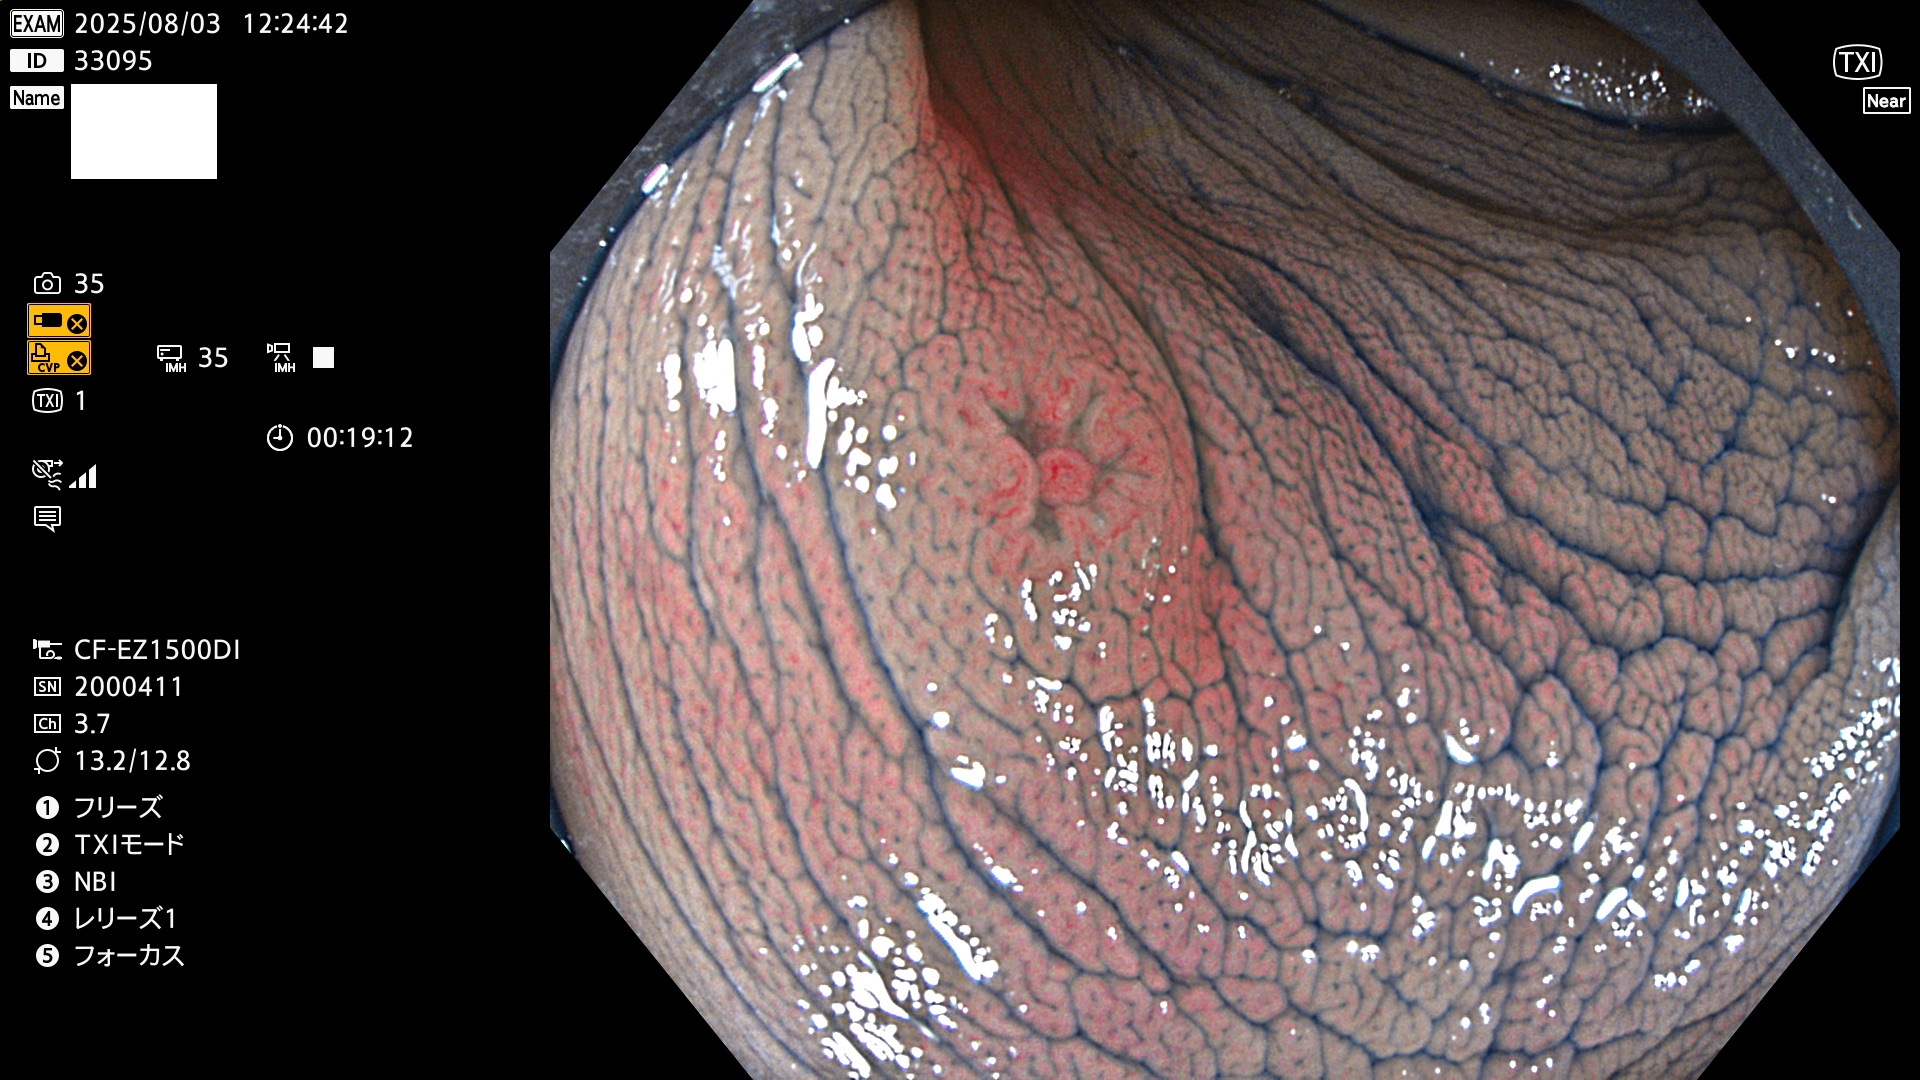

2025年7月31日〜8月3日の4日間(35件)5個 (Uc_ADR=5個/35人=14%)